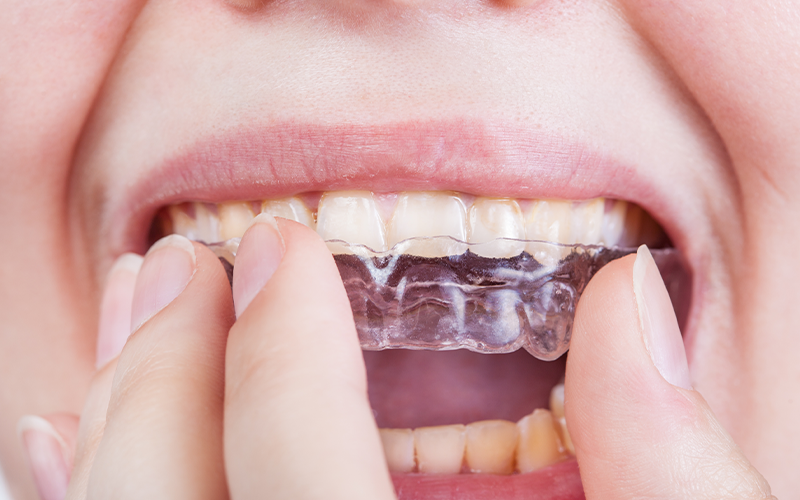

서울바른훈치과 이갈이 치료방법

서울바른훈치과에서는 임상검사 및 바이트스트립, 필요시 치과에서 제작한 이갈이 검사장치를 이용하여 이갈이를 정확하게 진단하고 이와 동반된 치아시림, 턱관절장애, 안면부 근육통, 두통, 사각턱까지 총체적으로 치료가 가능합니다.

• 이갈이

방지장치